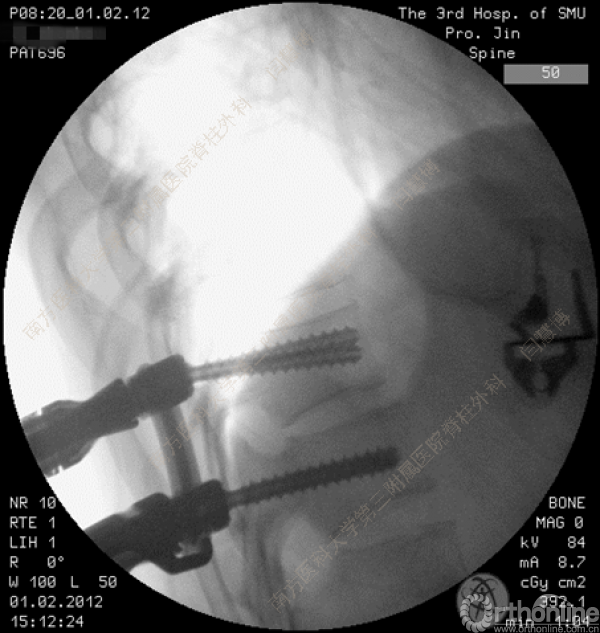

胸腰椎骨折是指由于外力造成胸腰椎骨质连续性的破坏,在如车祸、高处坠落等意外事故中,是最常见的脊柱损伤。老年患者由于本身存在骨质疏松,甚至有可能因为一些如滑倒、跌倒等低暴力因素导致胸腰椎骨折。胸腰椎骨折患者常合并神经功能损伤,且由于致伤因素基本为高能损伤,常合并其他脏器损伤,这为治疗带来了极大的困难和挑战。针对胸腰椎骨折,南方医科大学第三附属医院闫慧博教授介绍了他们运用微创方法治疗的经验。